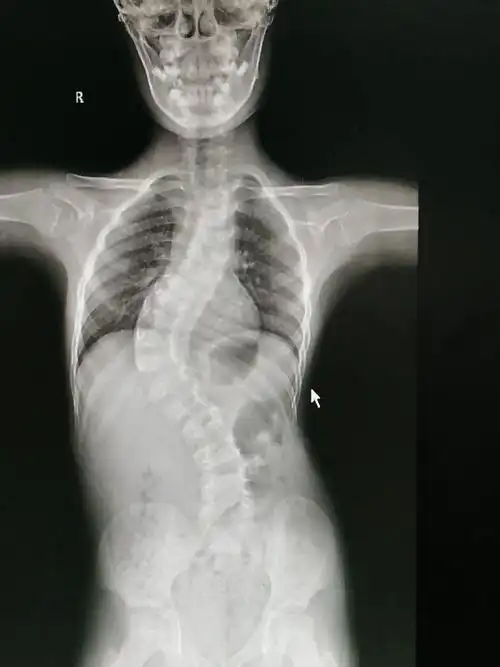

脊柱侧弯手术,患者应该怎样进行康复训练(脊柱侧弯手术后如何进行康复